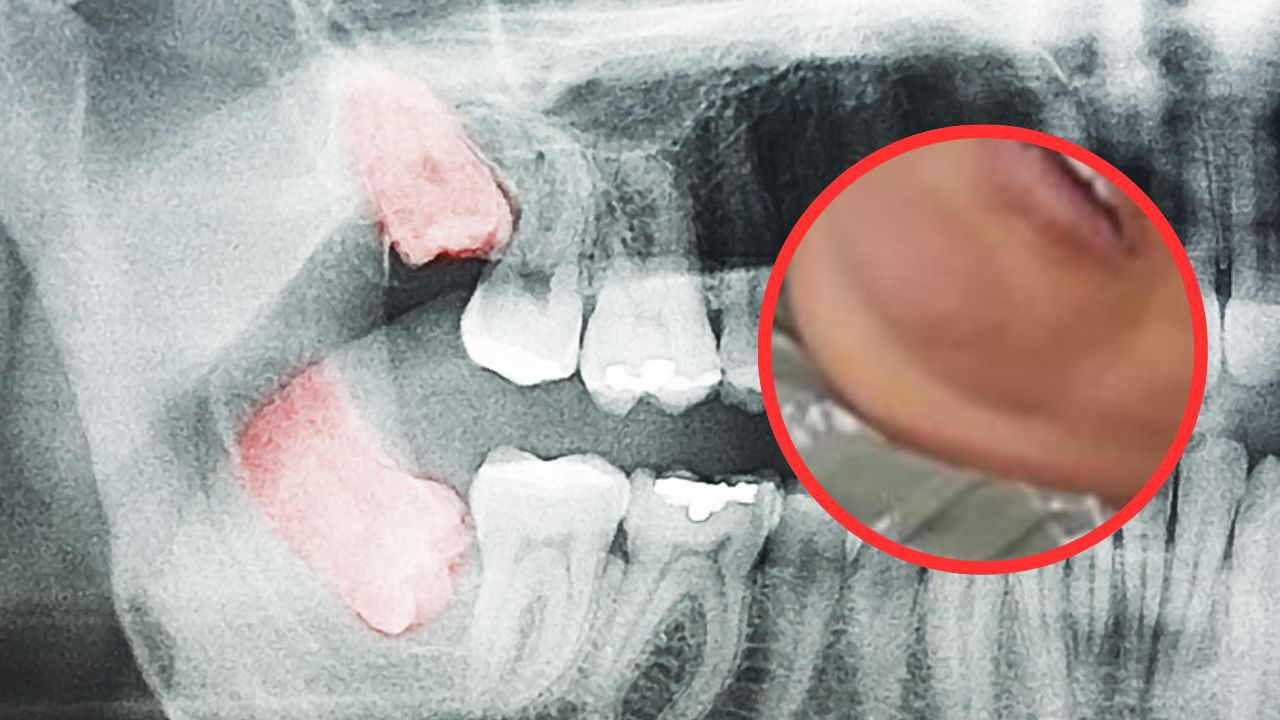

Se trata de Cristiana Elizabeth Lagos, originaria y residente del barrio El Porvenir en Choluteca, sur de Honduras, quien se encuentra supuestamente en estado de coma en el Hospital Regional del Sur tras presentar una neuroinfección a consecuencia de una infección en una muela.

De acuerdo con la información de La Hora de El Corpus, Lagos ingresó además al centro hospitalario con un cuadro clínico de diabetes e hipertensa no controlada.

Sin embargo, el Control Dental Europeo especifica que las muelas picadas, rotas y podridas son condiciones dentales comunes que pueden ser dolorosas e incómodas y, si no se tratan adecuadamente, también pueden provocar infecciones graves.